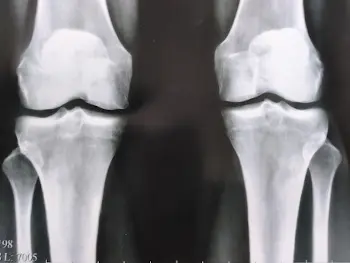

এই ছবিগুলো দেখো। সঠিক ছবিতে, জয়েন্টের জায়গা নেই, হাড়গুলো একে অপরের সাথে ঘষছে, যার ফলে তীব্র ব্যথা হচ্ছে। আর এই প্রক্রিয়া বন্ধ করা খুব কঠিন! কয়েক বছরের মধ্যে, ব্যক্তিটি অক্ষম হয়ে যাবে এবং নিজের যত্ন নিতে পারবে না।

এই সবই তরুণাস্থি টিস্যুকে নরম করে, জীর্ণ করে এবং পাতলা করে। প্রতিটি নতুন নড়াচড়ার সাথে, তরুণাস্থি জীর্ণ হয়ে যায় এবং বিকৃত হয়ে যায়, হাড়গুলি একে অপরের সাথে ঘষতে শুরু করে, যার ফলে অসহনীয় ব্যথা হয়।

রিউমাটয়েড আর্থ্রাইটিস এবং অস্টিওআর্থ্রাইটিস রোগ শুরু হওয়ার 3-5 বছরেরও কম সময়ের মধ্যে অক্ষমতা সৃষ্টি করতে পারে এবং আয়ু 15-20 বছর কমিয়ে দিতে পারে!